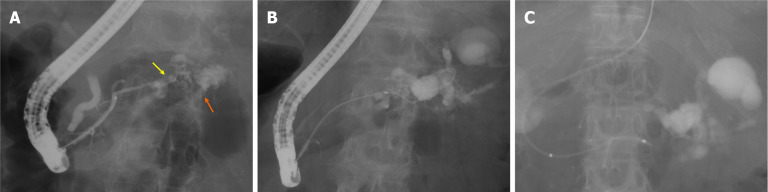

Case summary: A 74-year-old woman with pancreatic body and tail cancer developed fever and left-sided chest pain after multiple courses of chemotherapy. Computed tomography revealed fluid accumulation around the pancreatic tail and spleen along with a left pleural effusion. The effusion was diagnosed as reactive secondary to pancreatic fluid leakage. Endoscopic retrograde cholangiopancreatography identified irregular stenosis of the main pancreatic duct in the pancreatic body. Distal to the stenosis, the main ductal structure was nearly obliterated by the tumor. The contrast medium had leaked into the pancreatic fluid leakage area through several fine, disrupted ductal structures. The guidewire was successfully advanced through an extremely fine tract that was not the main contrast-filling route. Standard dilators failed to expand the rigid trans-tumoral tract. A second endoscopic retrograde cholangiopancreatography using a drill dilator successfully expanded the trans-tumoral tract, enabling endoscopic nasopancreatic drainage tube placement. Subsequently, the pancreatic fluid leakage and pleural effusion resolved.